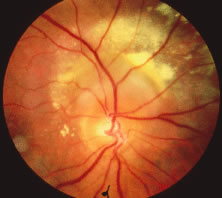

The ARN patient typically presents with progressive visual blurring in one or both eyes occurring over several weeks. These patients often are initially treated with corticosteroids, antitoxoplasmosis drugs, and other medications before arriving at the correct diagnosis. Examination reveals a prominent anterior uveitis that may be granulomatous or nongranulomatous (Fig. 1). Inflammatory signs may be prominent and cause severe pain (Fig. 2). The uveitis may be diffuse and so severe that it causes proptosis. These signs, and the diffuse vitreitis that makes the view of the retina difficult, may contribute to the high degree of delayed and/or misdiagnosis that occurs in the early stages of the disease. Significant vitreous cellular infiltration is seen in the presence of retinitis that is manifest by opacification of the retina, often most prominently in the periphery. Posterior pole involvement may include retinitis, as well as inflammation of the optic nerve head. Optic neuropathy might be the first sign of ARN with subsequent development of other retinal manifestations.8 Ultrasonography and computed tomography (CT) might be helpful in cases of ARN associated with optic nerve edema revealing enlargement of the optic nerve sheath.9 Even in ARN patients who are not immunocompromised and who have no clinical evidence of encephalitis, magnetic resonance imaging of selected cases has shown lesions of the lateral geniculate, optic tracts, and chiasma, which suggests that the virus spreads through the central nervous system (CNS) by axoplasmic transport from the retinal ganglion cells.10 A secondary retinal vasculitis is common, often accompanied by a mild number of retinal hemorrhages. Days to weeks after onset of the infection, the discrete peripheral lesions typically coalesce into a white or yellow ring of infected retina, and the associated vasculature is obliterated (Fig. 3). Necrotic retina desquamates into the vitreous resulting in vitreous sheets.3,6 Eventually, most untreated eyes can be expected to develop retinal detachment resulting from development of multiple full-thickness retinal breaks accompanied by traction or exudation.11 Giant retinal pigment epithelial tears have also been reported.12